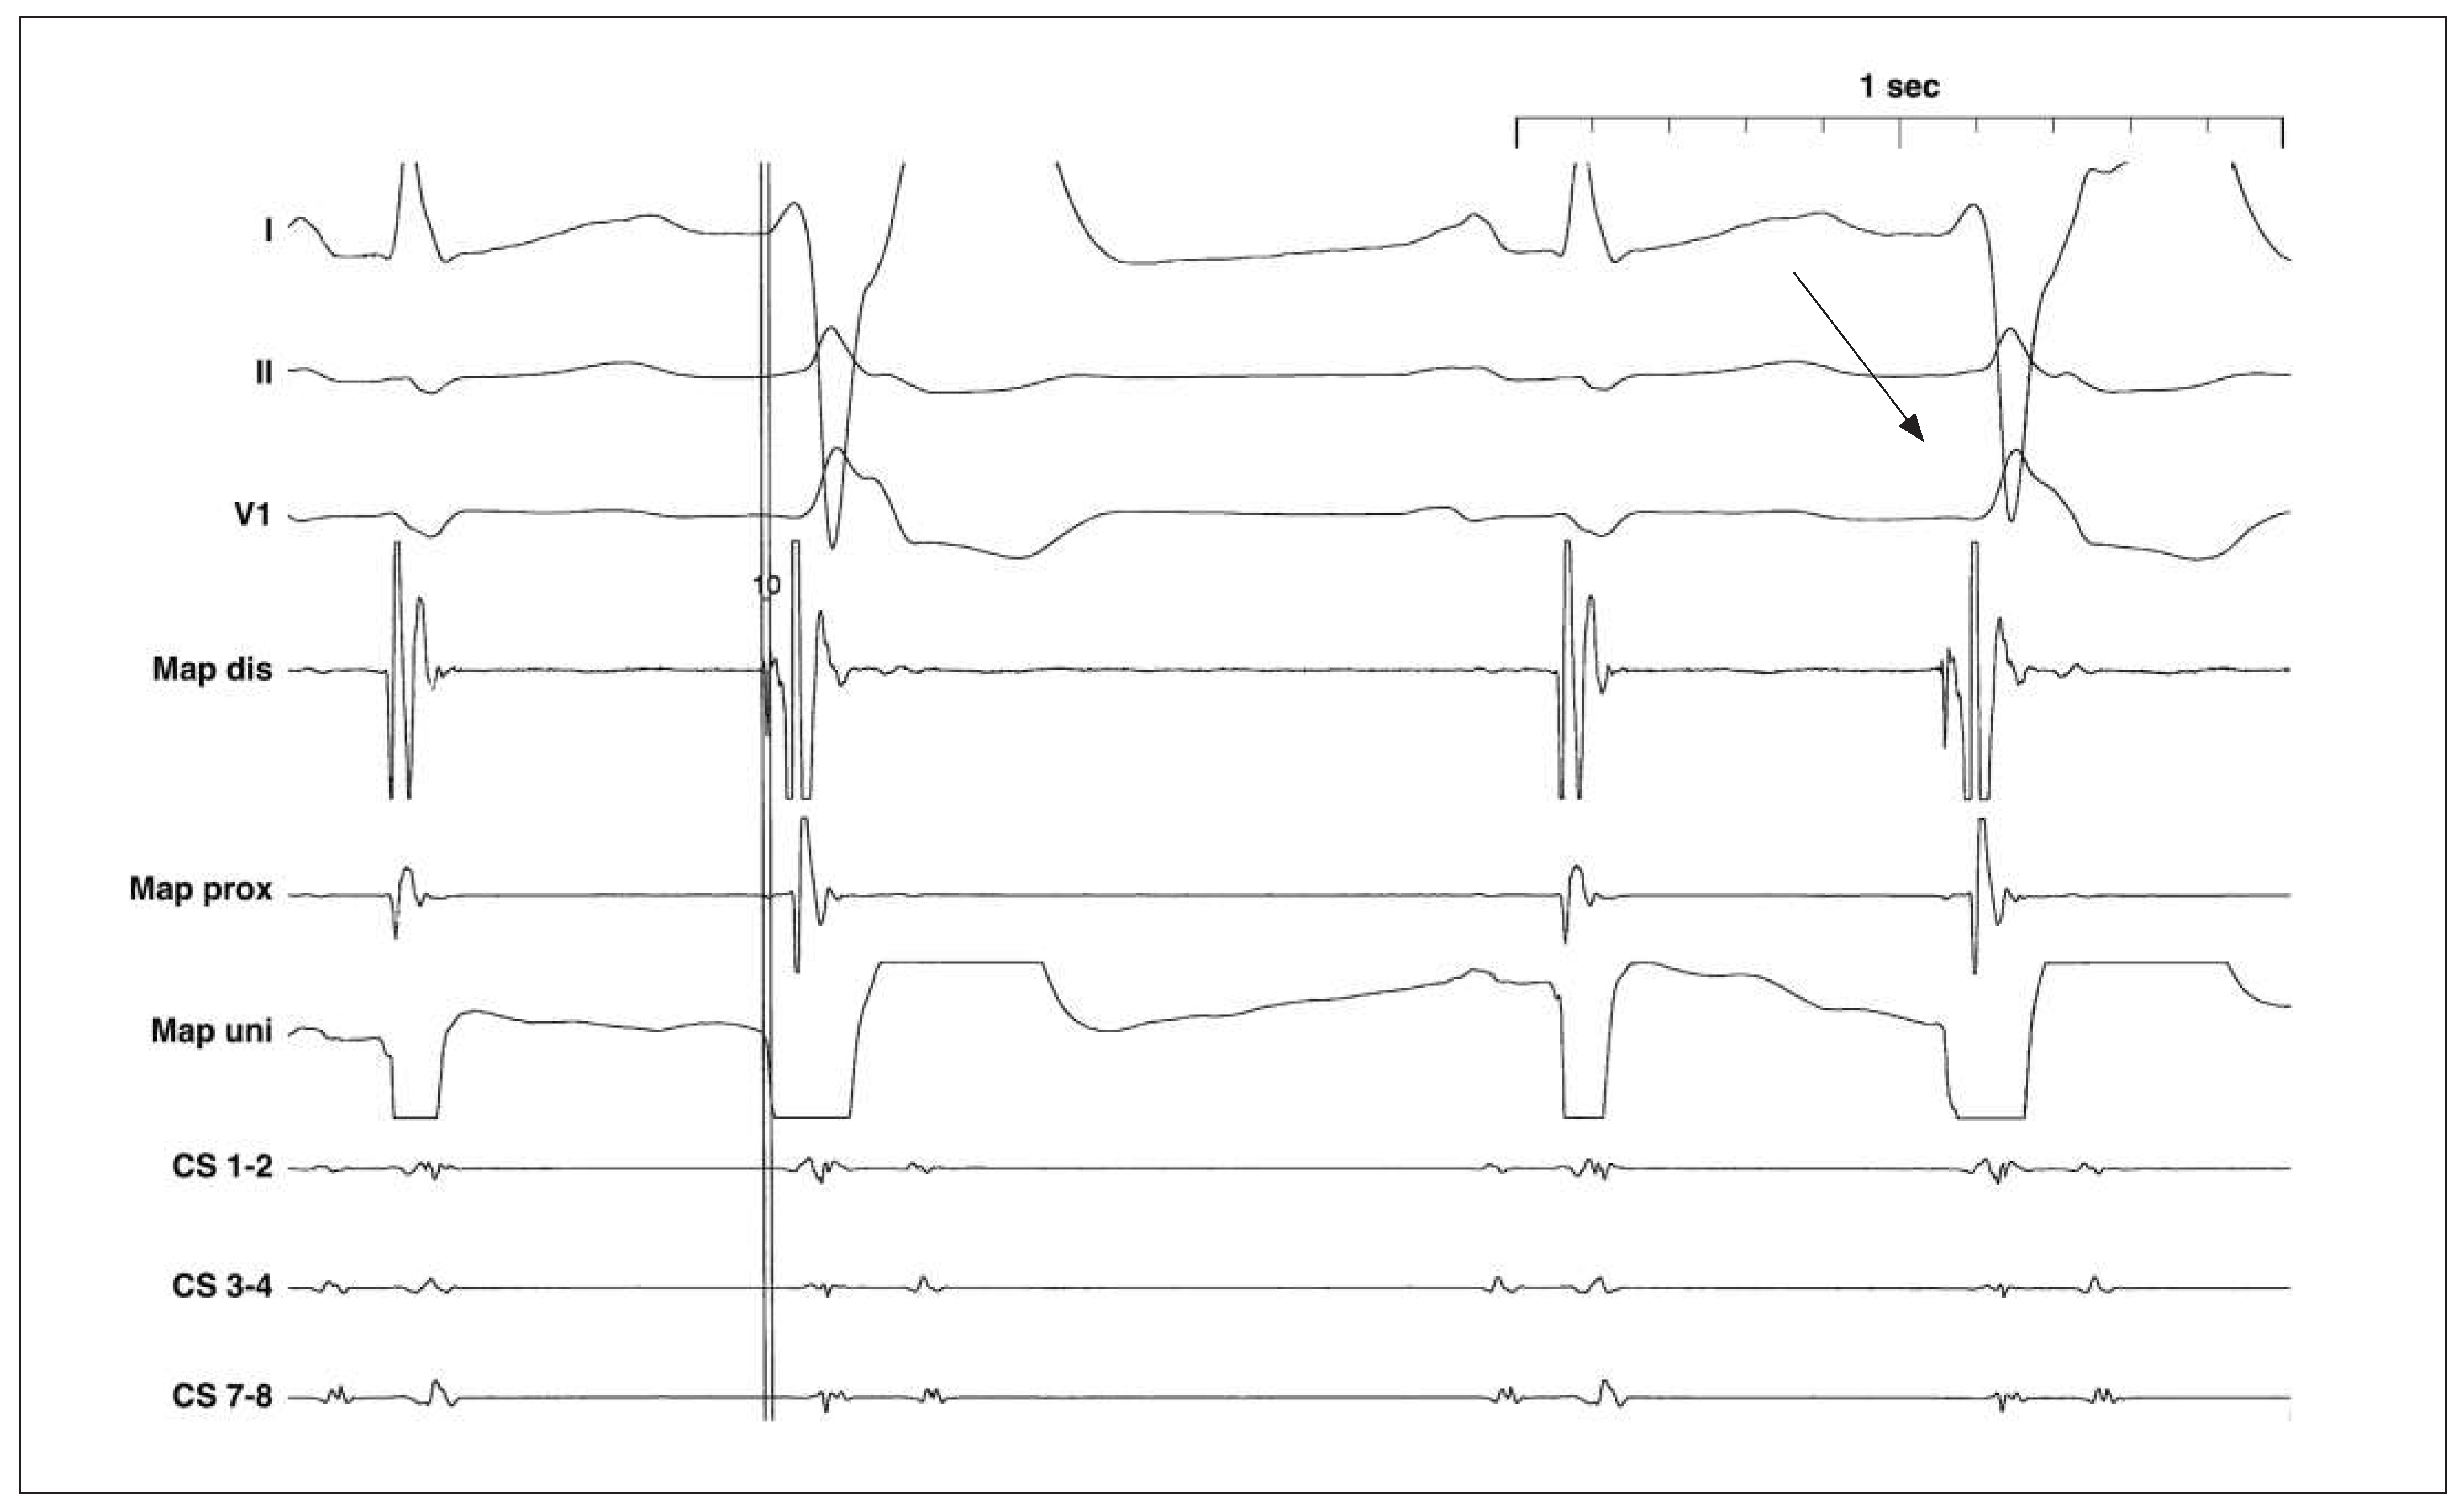

- Es fällt auf, dass die VES eine Rechtsschenkelblock(RSB-)Morphologie aufweisen (Rr’ in V1, tiefe und breite S-Zacken in I und V6). Daher ist von einem linksventrikulären Ursprung der VES auszugehen [1].